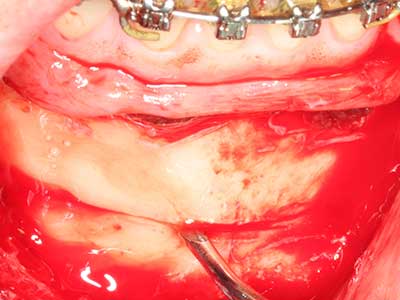

Quando le procedure chirurgiche vengono eseguite sull'osso nelle immediate vicinanze di strutture sensibili, come vasi sanguigni o nervi, gli strumenti rotanti pongono un rischio significativo di lesione iatrogena. I dispositivi piezoelettrici possono essere utili per la preparazione delle coperture ossee e la rimozione del tessuto duro in prossimità dei nervi, in particolare per la loro esposizione dopo una lesione iatrogena, ma anche durante la lateralizzazione dei nervi per le procedure di resezione e ricostruzione o il posizionamento di impianti (figg. 17-20). Il contatto leggero tra puntina piezoelettrica e nervo non causa generalmente danni, ma se si procede senza prestare attenzione con movimenti a sega o raccordi con residui di substrati ossei possono verificarsi danni al nervo temporanei o anche permanenti. Il rischio di danno, tuttavia, è considerato sostanzialmente inferiore al rischio presente utilizzando seghe o frese (Pereira, Gealh et al. 2014).